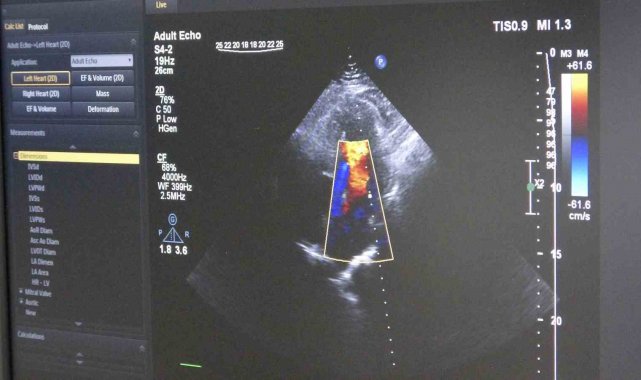

Gelişen teknolojiyle birlikte öne çıkan tedavi yöntemlerinden biri olan ilaç kaplı balon uygulaması, damara kalıcı metal yapı bırakmadan tedavi imkânı sunuyor. Bu yöntemde, özel ilaç kaplı balon damar içerisinde genişletilerek hem darlık gideriliyor hem de ilaç doğrudan damar duvarına etki ediyor.

Ordu Eğitim ve Araştırma Hastanesi Kardiyoloji Kliniği'ne göğüs ağrısı şikâyetiyle başvuran 55 yaşındaki erkek hastada yapılan anjiyografide, 3 damarda ileri derecede darlık tespit edildi. İlk değerlendirmede hastaya bypass ameliyatı önerildi. Ancak hastanın ameliyatı kabul etmemesi üzerine alternatif tedavi seçenekleri değerlendirildi. Yapılan detaylı incelemeler sonucunda hasta için ilaç kaplı balon yöntemiyle girişimsel tedavi planlandı. Uygulanan işlemle hastanın 3 damarındaki tıkanıklıklar stent kullanılmadan açılırken, hasta ise tedavinin 2'nci günü taburcu edildi.

Tedavi sürecinde damar yapısının ayrıntılı incelendiğini belirten Dereli, "İşlem öncesinde intravasküler ultrason (IVUS) ile damar duvarını değerlendiriyoruz. Ayrıca fraksiyonel akım rezervi (FFR) ile darlığın kan akımına etkisini ölçüyoruz. Bu yöntemler, doğru karar vermemizi ve başarılı sonuç elde etmemizi sağlıyor" diye konuştu.